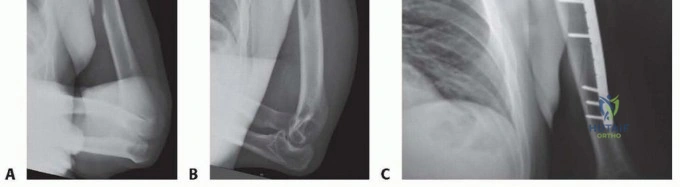

Fracture Reduction and Plate Fixation

Once the fracture site is exposed and the hematoma evacuated, reduction is achieved using longitudinal traction, rotation, and direct manipulation with bone reduction forceps. Soft tissue interposition, particularly from the brachialis or triceps, must be cleared from the fracture ends.

For simple fracture patterns (transverse or short oblique), absolute stability is the goal. If the obliquity allows, an interfragmentary lag screw is placed perpendicular to the fracture plane to generate interfragmentary compression. A 4.5 millimeter narrow plate is then contoured to the anterolateral aspect of the humerus. The plate is applied in a neutralization mode. If a lag screw cannot be placed, the plate is applied in a dynamic compression mode utilizing eccentrically drilled screws.

For comminuted or segmental fractures, relative stability is preferred. The fracture zone is bypassed without disturbing the comminuted fragments, preserving the local biology. A longer plate is utilized to span the fracture, acting as a bridge construct. Locking screws are highly beneficial in this scenario, particularly in osteoporotic bone, as they provide angular stability and reduce the risk of hardware pullout.

Clinical & Radiographic Imaging